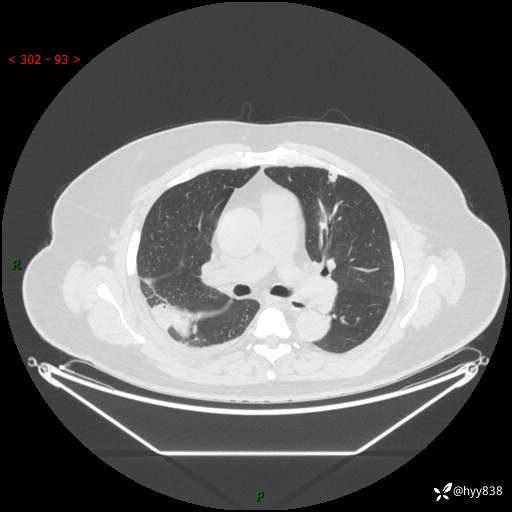

性别:男

年龄:48岁

简要病史:发热来诊(门诊病人)

胸部CT平扫